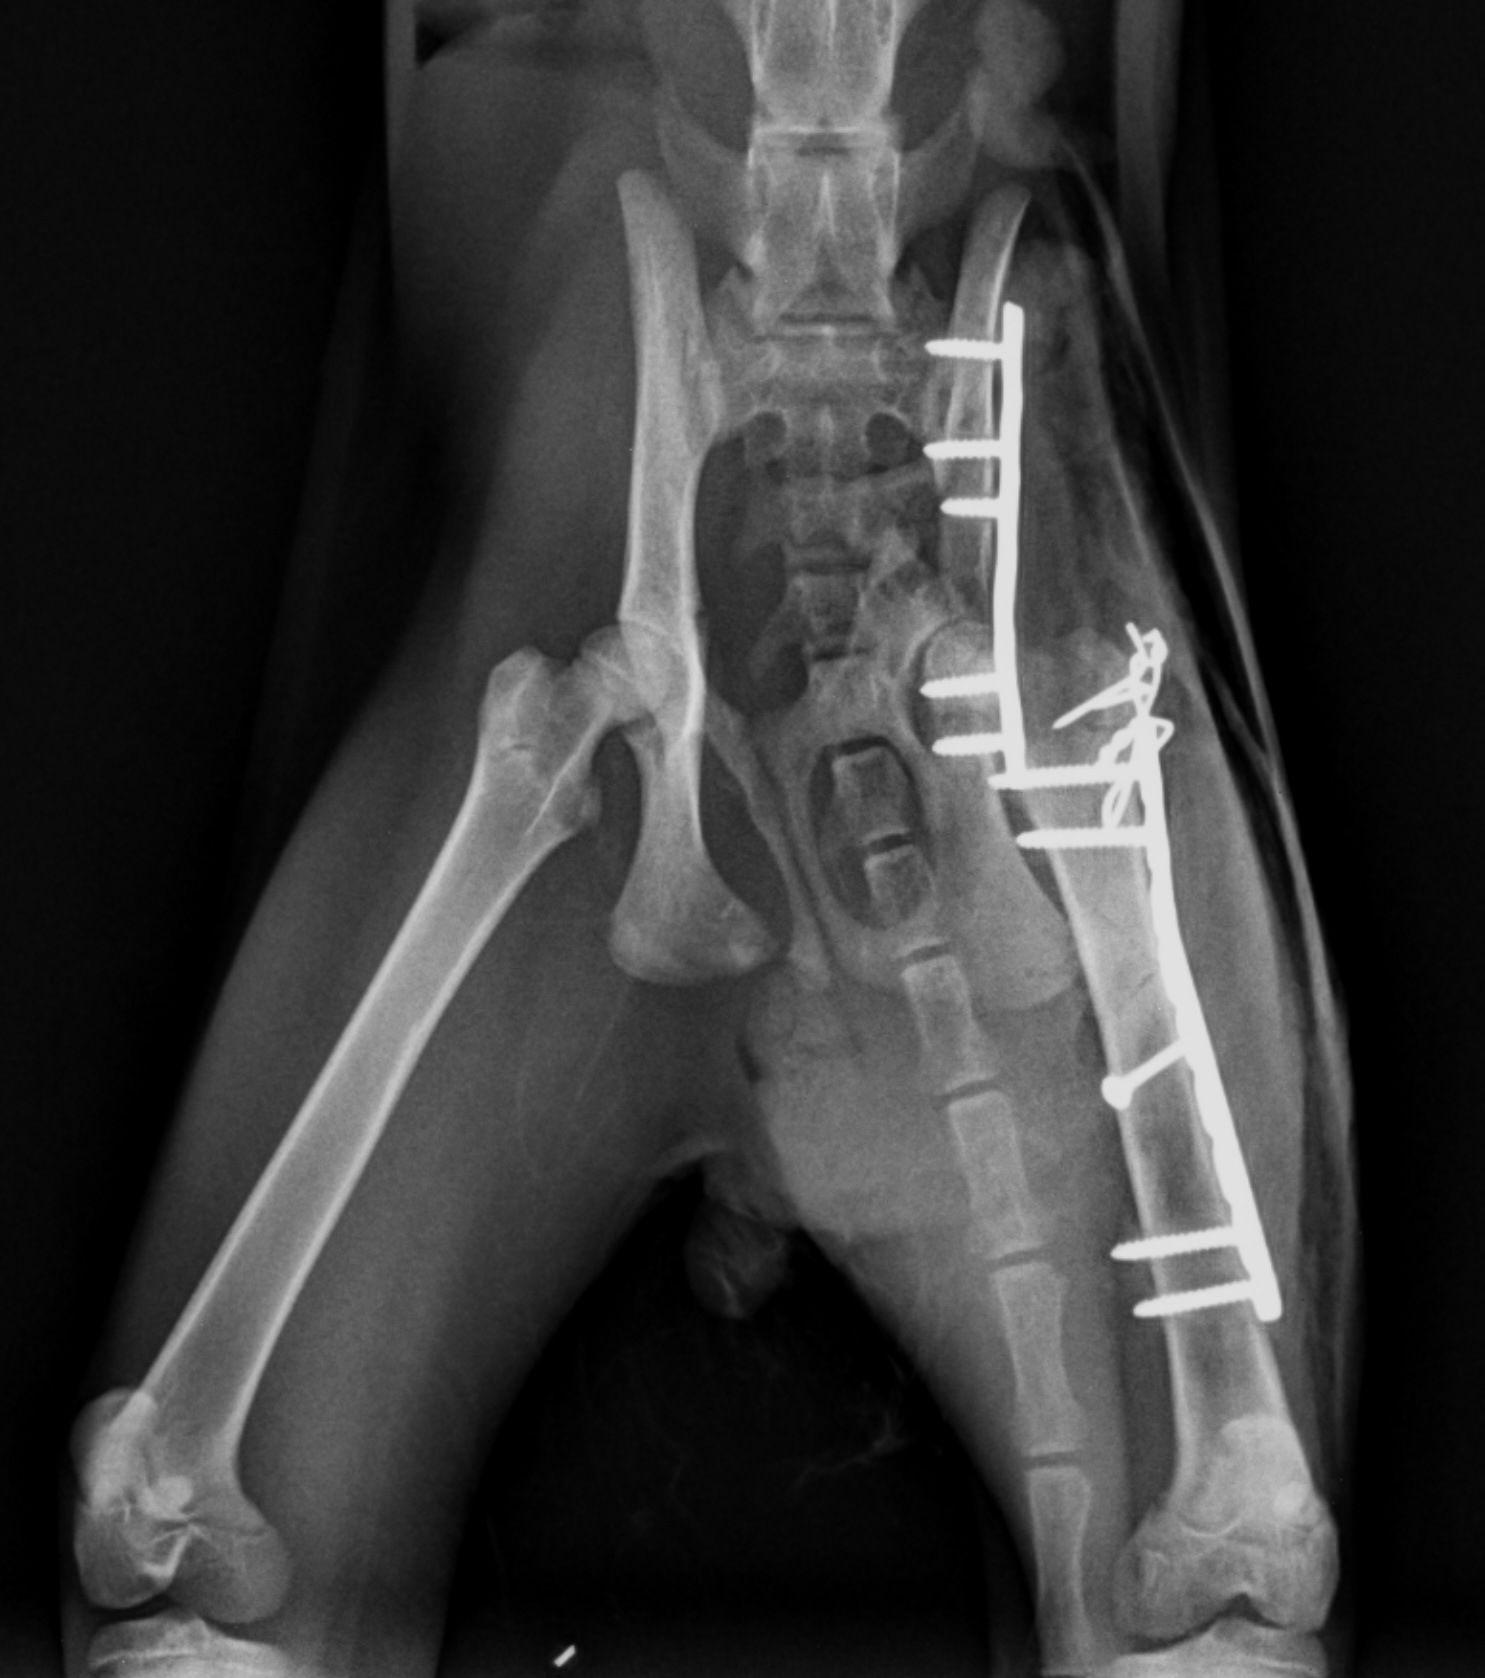

最近は屋内で飼育されている猫が増えてきたせいか交通事故に合う猫も少なくなったなぁ・・なんて思っていたら久しぶりになかなか激しい症例が来院しました。これだけ激しい骨折にも関わらず血液検査はオールクリア。早速手術に取り掛かることにしました。ただでさえデリケートな手技を行わねばならない骨盤骨折は、骨折している部位に到達するにあたり正常な部位にも骨切りをしてアプローチしなくてはならないのでなかなかスタミナと忍耐力が必要な手術です。今回は大腿骨も骨折していたのでまずはアプローチしやすい大腿骨をロッキングプレートで固定、続いて骨盤骨折整復という流れで手術を行いました。正味3時間の手術でしたが術後2日目には立って食事を食べられるようになりました。骨盤という骨はなかなか形態が複雑で整復するのに苦労しますが、歩けるようになって退院する姿を見ると疲れも吹っ飛んでいきますね。